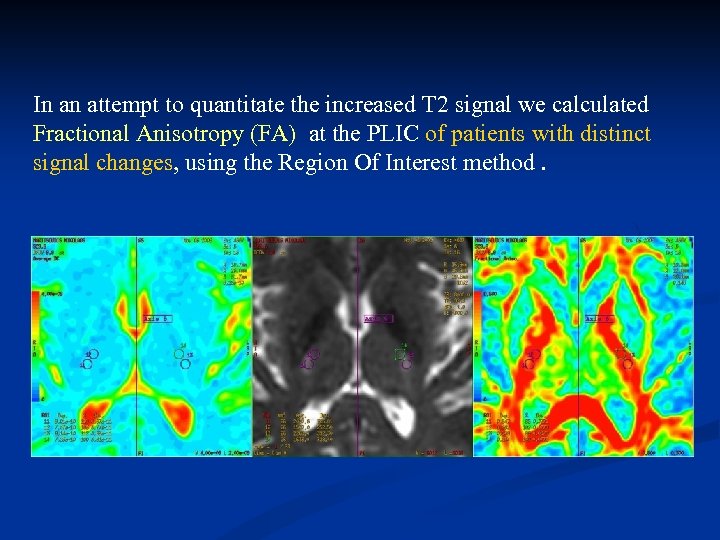

In an attempt to quantitate the increased T 2 signal we calculated Fractional Anisotropy (FA) at the PLIC of patients with distinct signal changes, using the Region Of Interest method.

In an attempt to quantitate the increased T 2 signal we calculated Fractional Anisotropy (FA) at the PLIC of patients with distinct signal changes, using the Region Of Interest method.